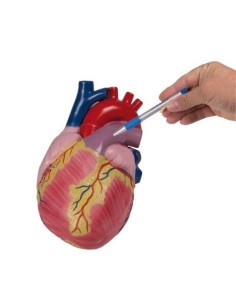

Dal cranio in 22 parti con incastri magnetici ai modelli di colonna vertebrale, da quelli di articolazioni a quelli di cuore, ogni pezzo della nostra collezione è progettato per un’immersione totale nello studio dell’anatomia umana. I nostri modelli, realizzati tramite scansioni di ossa vere, garantiscono un’esperienza tattile autentica e una fedeltà di peso quasi identica agli originali.

Essenziali per studenti e professionisti, i nostri modelli anatomici sono strumenti didattici che permettono di osservare le strutture anatomiche con precisione, eliminando la necessità di dissezioni o studi invasivi. Sono inoltre utili per spiegare ai pazienti le patologie, rendendo la comunicazione più efficace e risparmiando tempo prezioso.